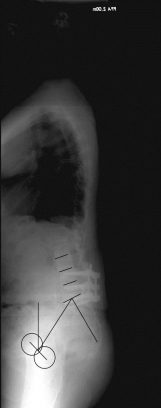

Adulte Def. IAdulte Def. II

X-ray image before and after surgery. The patient underwent spinal surgery at another hospital and increasingly developed other complaints. The X-ray showed a complete loss of the hollow back and a resulting change in balance. A so-called lordosis operation led to a restoration of a normal hollow back and thus a normal spinal balance and finally to regressive complaints.